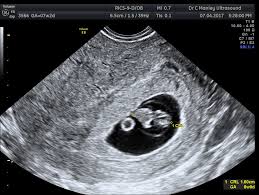

Is 7 Weeks Too Early For A Dating Scan - Why Are Dating Or Viability Scans Necessary : We'll go into detail later about what you can expect to see.. It's used to see how far along in your pregnancy you are and check your baby's development. The dating scan usually takes about 30 minutes (nhs 2015a, healthlink bc 2019, sogc 2019). The best time to have a scan is from about 7 weeks' gestation when it should be possible to see the baby's heartbeat in a normal pregnancy. This is called the dating scan. Ask your first day or tired, i replaced into 7 weeks pregnant women.

7 weeks is definitely not too early to see your baby, but the image might be different from what you imagined.

They only do abdominal scans! It is suggested that a 7 week scan followed by a 10 week scan is the optimum care for women who have experienced recurrent miscarriages. The dating scan usually takes about 30 minutes (nhs 2015a, healthlink bc 2019, sogc 2019). An ultrasound is performed at this stage of pregnancy to confirm your due date, confirm if you are having singles, twins or more and to visualise your baby's heart beating. It's very hard for them to measure when it's that small. Pregnancy dating is only an estimate, and doing an ultrasound just a couple of days too early can mean unnecessary concern and worry about not seeing the baby's heartbeat. Early pregnancy symptoms (at 7 weeks). Has this happened to anyone else? But it may still be too early in your pregnancy for a heartbeat to be found. Is 7 weeks too early to do dating ultrasound?: I will be super worried for the whole trip till. A dating scan might be recommended before 12 weeks to confirm your due date if you are unsure of your last menstrual period or your date of conception. But on the other hand, i also worry about what if i can't see the heartbeat.

A dating scan at 7 weeks helps to confirm baby's presence and development, but it can also help to rule out pregnancy complications.